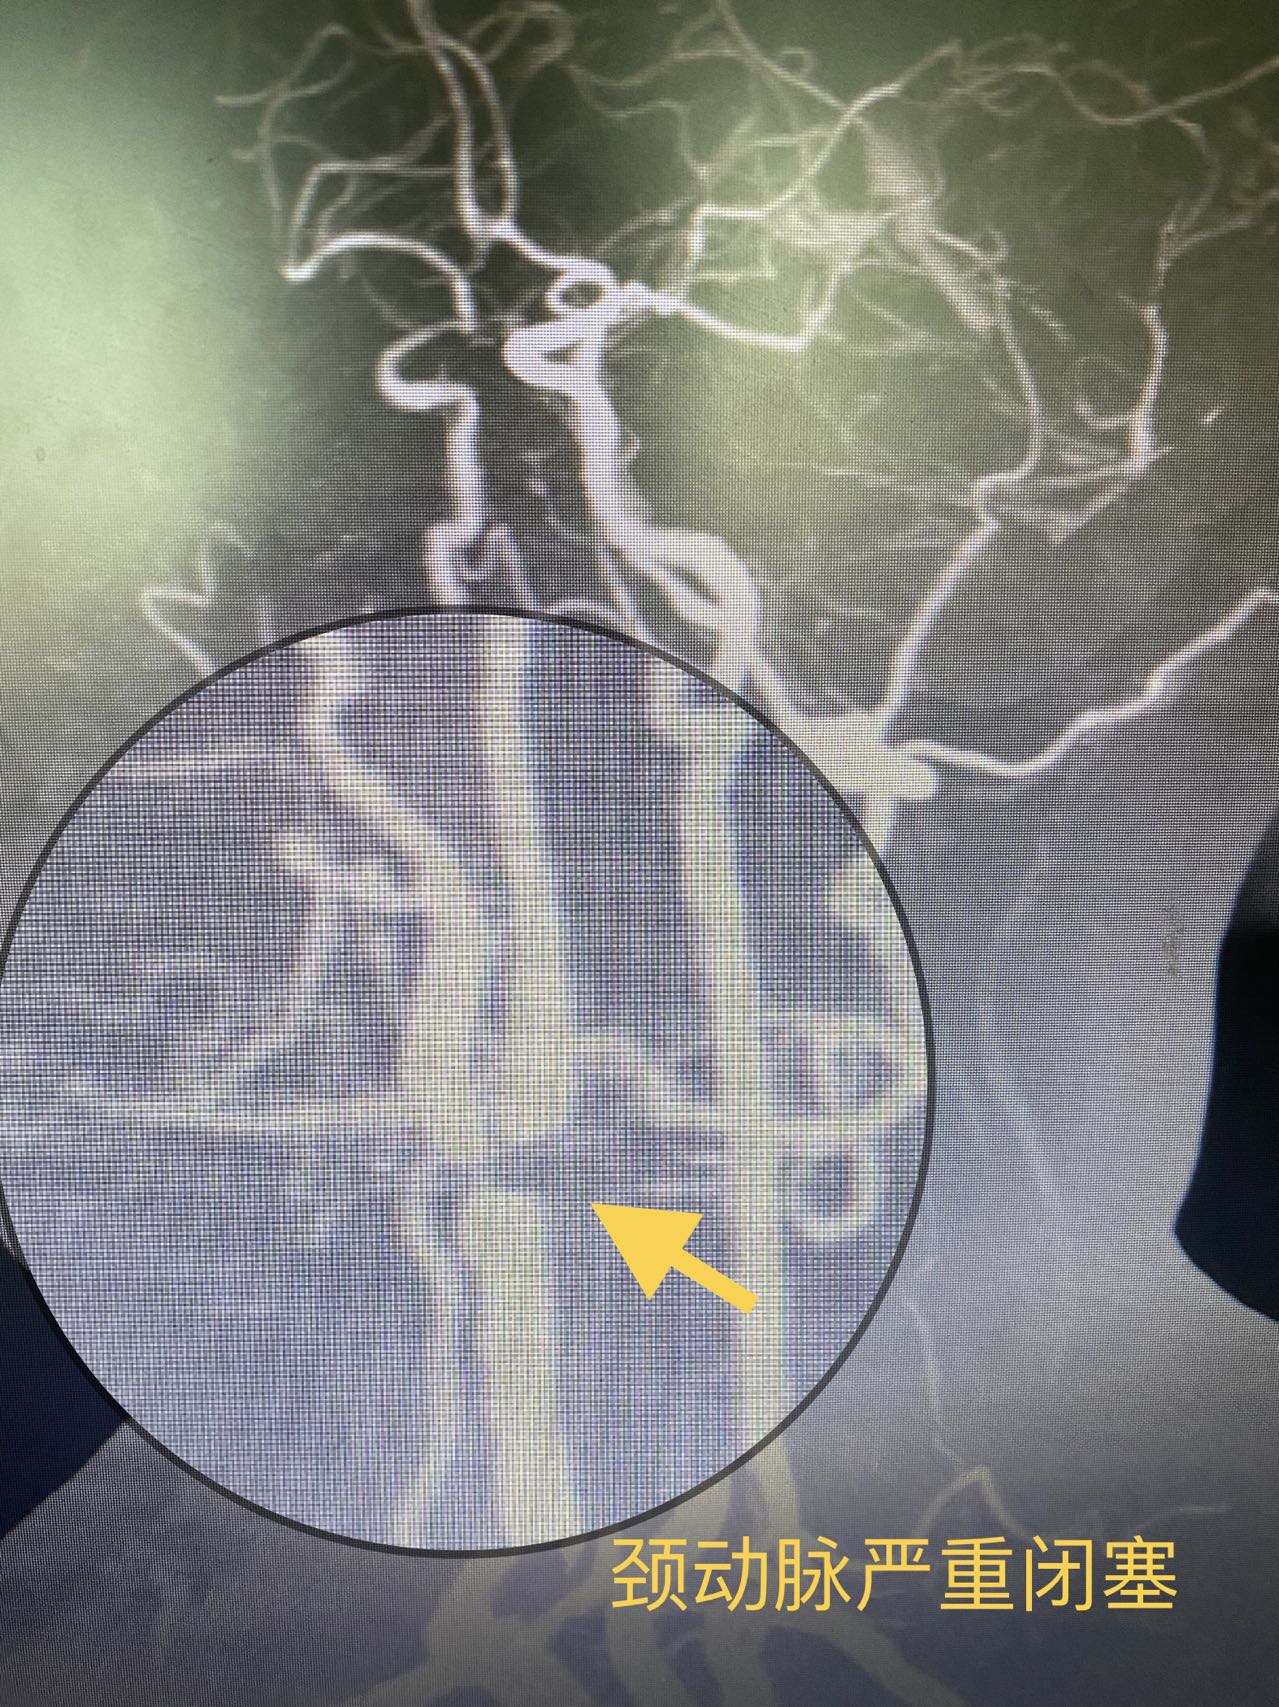

曹大姐在黑朦严重后到湖南省人民医院集团澧县人民医院就诊,通过超声检查发现存在严重的颈动脉病变,右侧颈动脉基本闭塞,继而转诊至介入血管外科。通过后续的脑部血管及血运评估发现,曹大姐右侧的大脑供血明显比左侧差很多,已出现明显的缺血症状。

湖南省人民医院派驻常德澧县人民医院挂职的颜鹏副院长介绍,曹大姐的眼病其实是一种脑缺血的表现,右侧颈动脉闭塞后可以导致右侧眼动脉供血不足,也可以导致右侧大脑缺血。这种黑朦反复发作是身体向我们发出的警告,如果没有得到重视,很快会发展成脑梗塞,也就是常说的的中风,可能会导致偏瘫,生活不能自理等一系列功能障碍,甚至危及生命。曹大姐的黑朦症状频繁发作,也提示堵塞血管的斑块很不稳定,如果采用腔内支架手术,术中发生斑块脱落,导致脑梗的风险极高,因此颜鹏副院长决定采用颈动脉内膜剥脱及血管吻合技术重建病变的颈动脉。通过与麻醉师制定详细的手术规划后,曹大姐顺利接受了手术治疗,苏醒后,她的言语及肢体活动均无异常,自觉眼睛也比以前明亮多了。